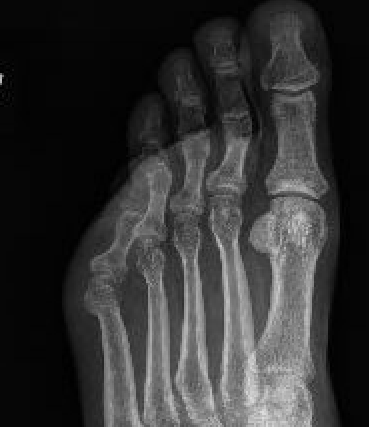

5th toe adducted & overrides 4th toe

Dorsomedial subluxation of the MTPJ